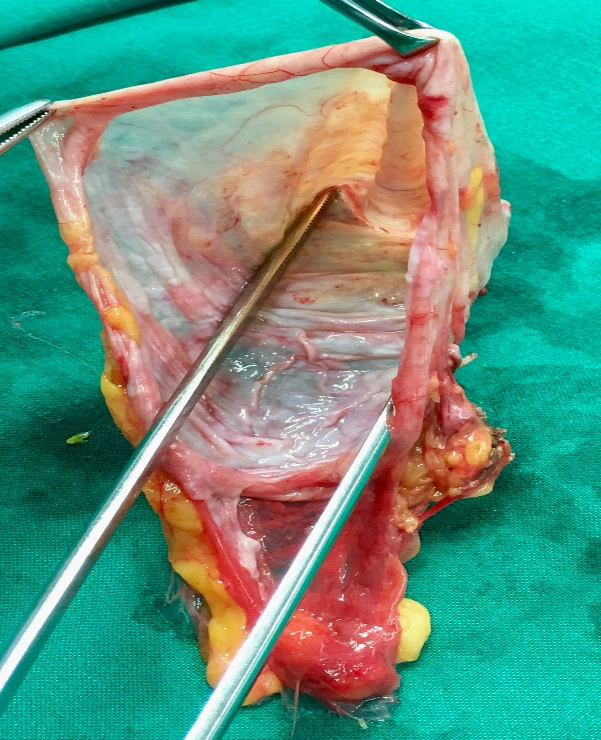

Multidisciplinary team (MDT) meeting recommended to attempt laparoscopic approach; since investigations revealed no biologic or radiologic potentially malignant features. Patient was consented for laparoscopic cholecystectomy and resection of the cystic mass with the possibility of conversion to laparotomy. She was placed in the reverse Trendelenburg with right up tilt position and the procedure was performed using three trocars only (two 5 mm and one 10 mm ports). Initial exploration revealed a large bulge within the mesentery of the right colon (Figure 2). Liver and peritoneal surfaces were examined and noted no abnormality. Adequate exposure was attained using Cattel maneuver (medial visceral rotation of right-sided organs). The uterus and both ovaries looked normal, no attachment with the cyst was identified. Gallbladder was retracted upward and the large cystic lesion was entirely visualized. It appeared to be an oval, thin walled and transparent. It had a regular border with smooth glistening surface containing about 500 ml of serous material. Cyst was easily separable from the adjacent organs. It was totally dissected from the inferior border of the liver and right kidney down to the right iliac fossa. Complete excision of the cyst was done followed by cholecystectomy. The cyst wall components and gallbladder were retrieved through the umbilicus (Figure 3). All her symptoms were disappeared after surgery.

Histopathologic section revealed a thin walled multilocular cyst lined by tall columner cells with clear cytoplasm and basal nuclei along with low cuboidal cells resembling mesothelial cells. The stroma is densely cellular and collagenous, composed mainly of spindle cells. Microscopic examination was suggestive of mucinous cystadenoma with ovarian like stroma (Figure 4) No atypia or architectural complexity or any invasion was detected. Patient had an uneventful fast track recovery and 4 years' follow-up revealed no evidence of recurrence.

Figure 3:Gross Appearance of the cyst.